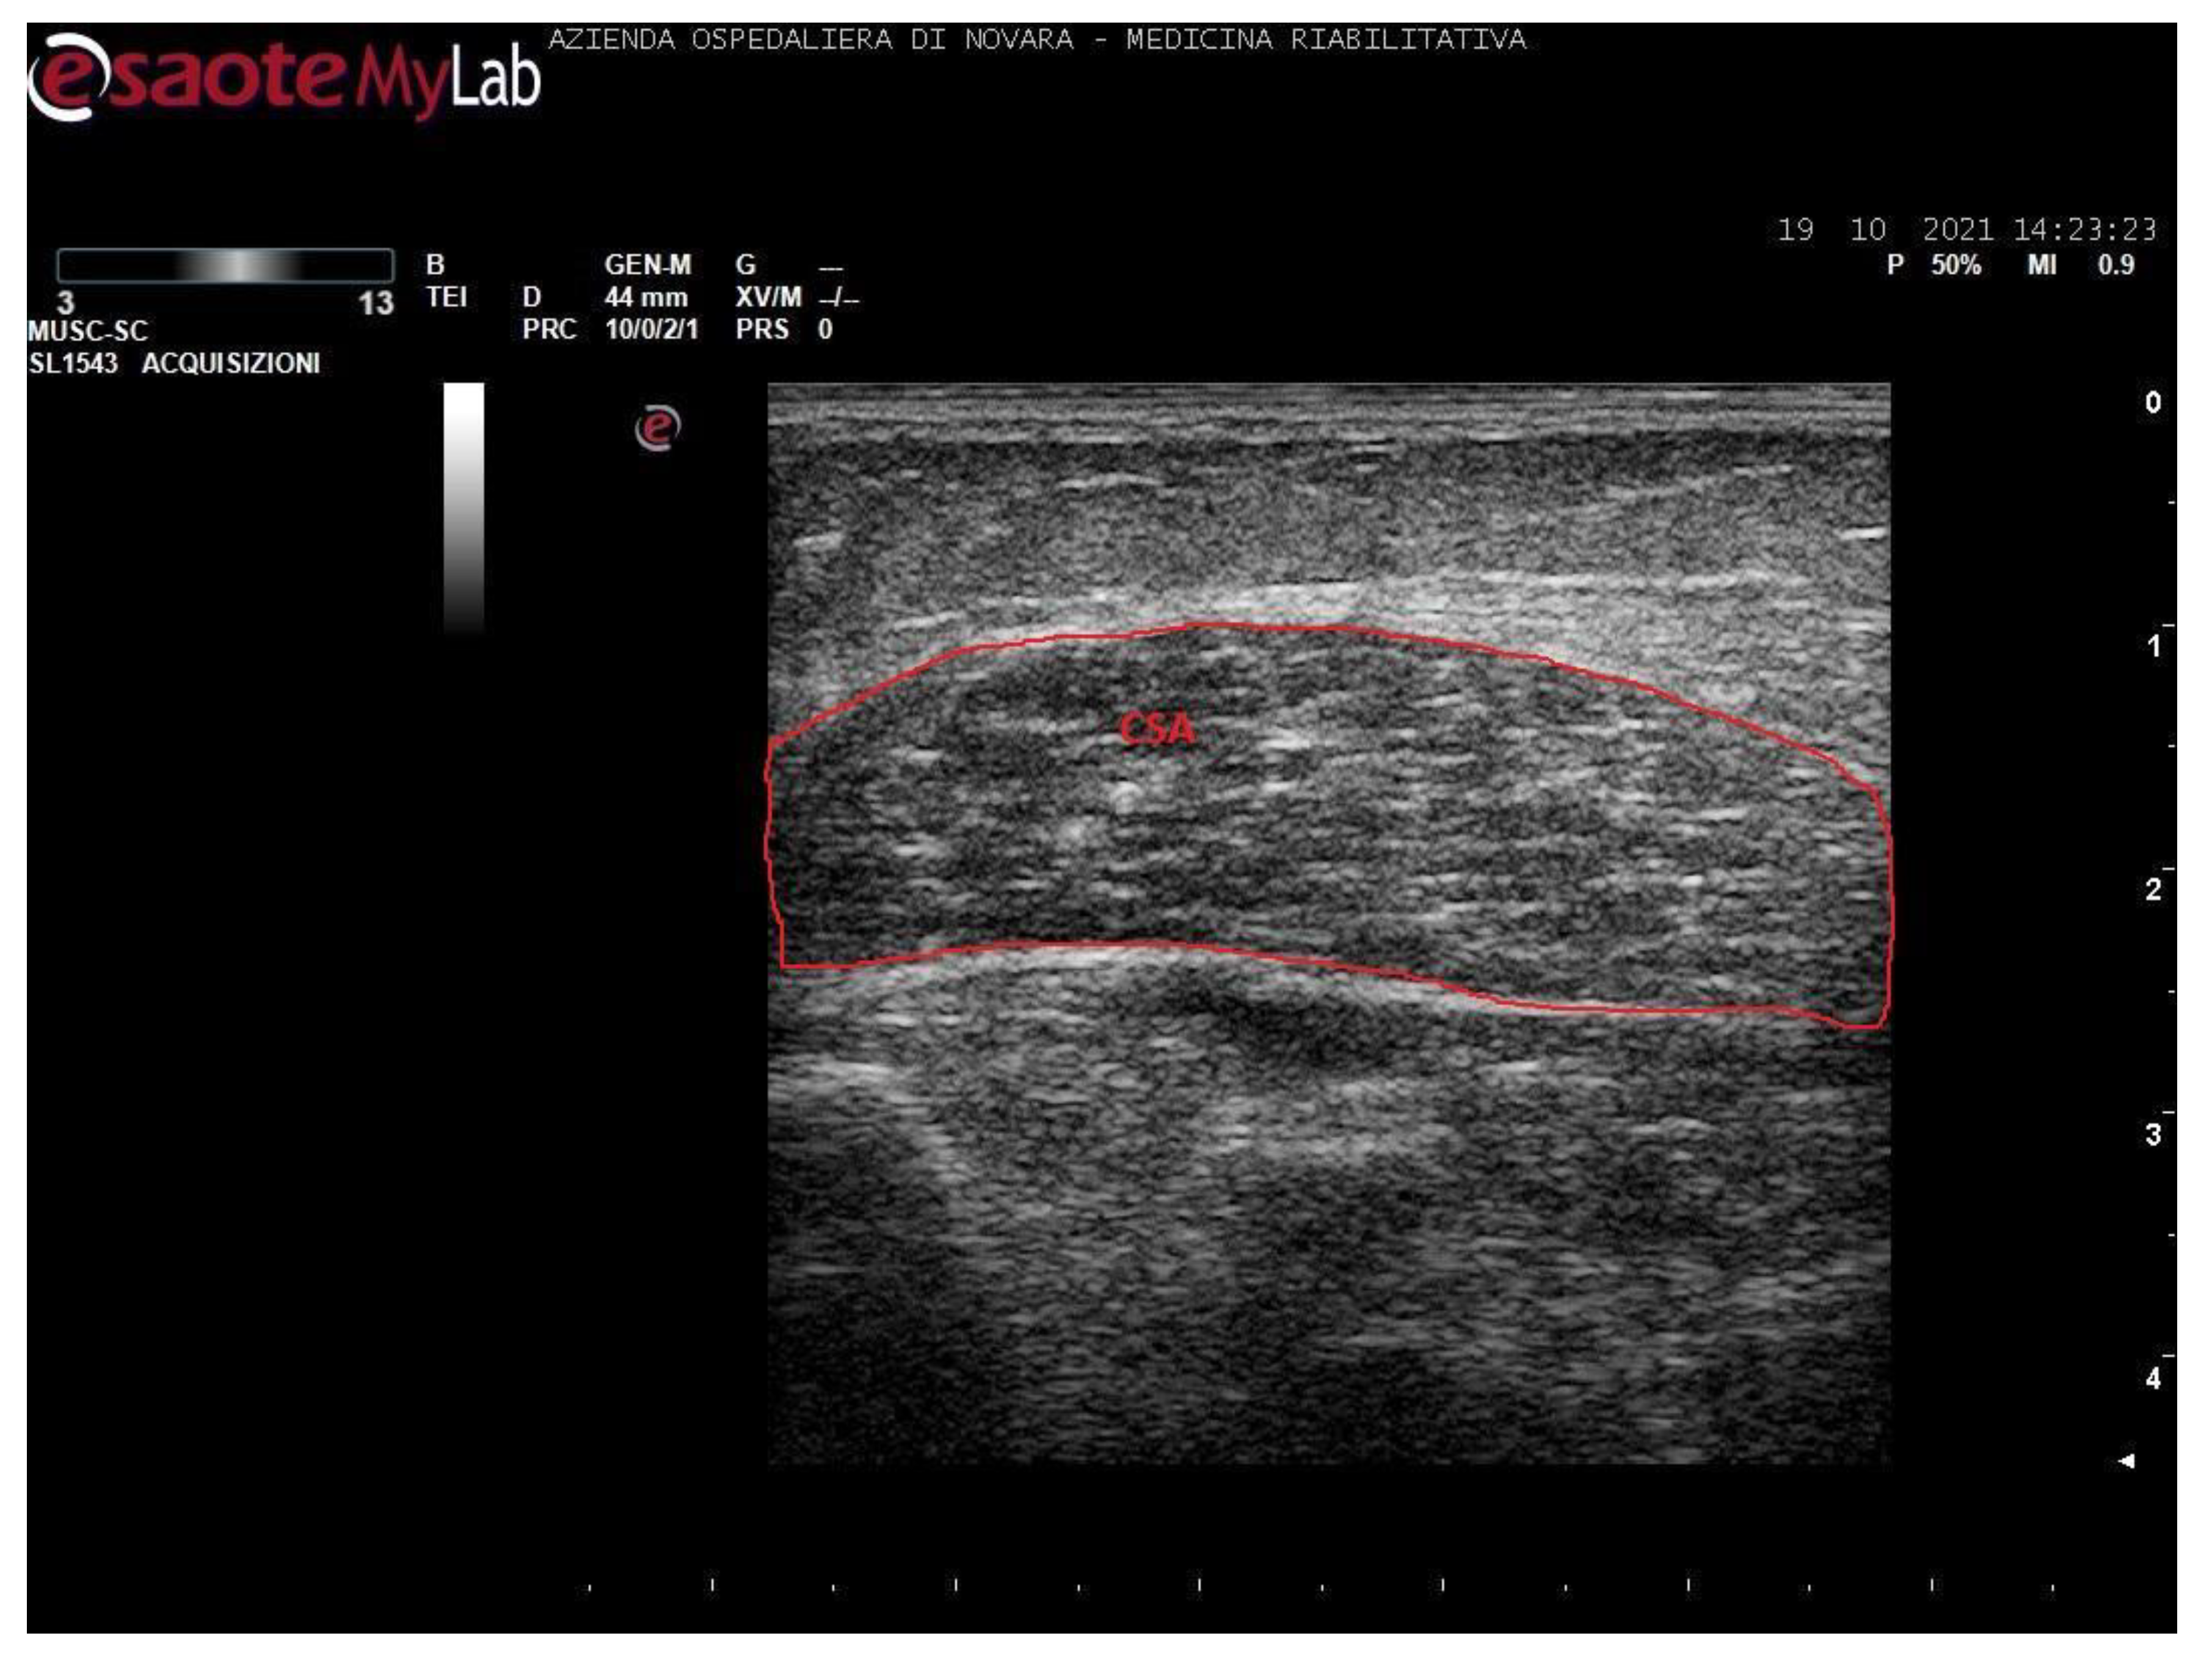

We acquired images of the medial gastrocnemius (MG) and soleus (SOL). Images were processed through the software ImageJ (National Institutes of Health, USA) in order to measure the muscle thickness (MT, cm), the cross-sectional area (CSA, cm2), the pennation angle (α, °), and the mean gray value (MGV, range 0-255). MGV was assessed considering the whole muscle longitudinal section as region of interest (ROI). The gray scale spreads from 0 (black) to 255 (white).

Measurements were taken as shown in Figure 1, Figure 2, Figure 3 and Figure 4.

Notably, soleus CSA presents several technical issues for its measurement. Firstly, in most cases, it is impossible to incorporate the entire area of such a wide muscle in the ultrasonographic frame. Secondly, the deep aponeurosis of SOL does not appear to be uniformly defined in transversal sections of long-standing degenerated spastic muscles, thus preventing an accurate profile definition. For these reasons, the authors preferred not to include such a biased value in this paper. The techinique of SOL CSA measurement was anyway reported in a healthy muscle in Figure 3 for illustrative purposes.

Figure 3. Ultrasound image of soleus in transversal section. In red: cross-sectional area (CSA).